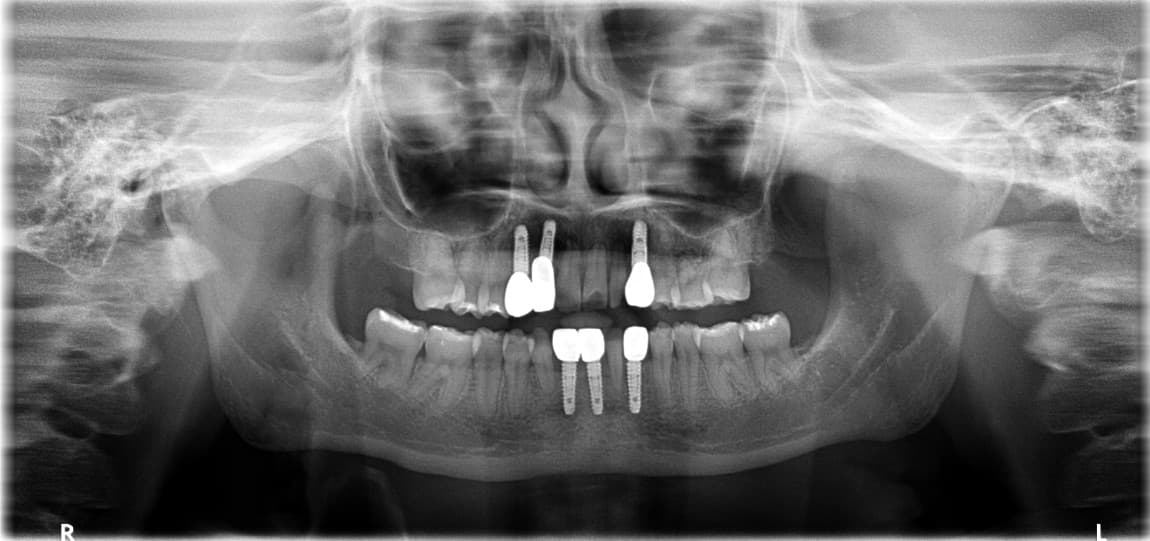

Digital Guided

Implant Before & After

Front Teeth Implant · Ms. K●● · Female, 50s

Front Teeth Implant · Mr. L●● · Male, 60s

Molar Implant · Mr. P●● · Male, 50s